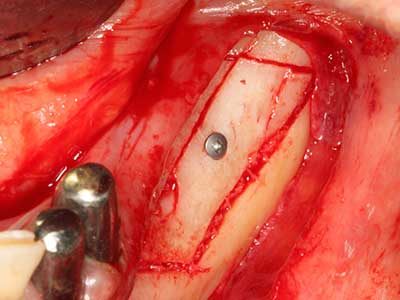

Fig. 18: Preparation of a cortical cover with the piezo bone saw (Piezomed, W&H).

Fig. 19: Surgical site after neurolysis and removal of osteoma.

Fig. 20: The removed bone cover is re-adapted and fixed with an osteosynthesis screw (KLS Martin, Tuttlingen).